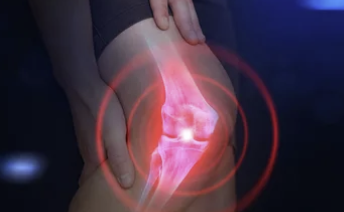

1. 무릎에 물이 찼다는 건 어떤 상태일까?

무릎 관절은 여러 층의 구조로 되어 있어요.

관절 안쪽에는 윤활액이라는 액체가 있는데, 이 액체는 평소에는 소량만 있어 관절을 부드럽게 움직이는 데 도움을 줍니다.

그런데 염증이나 손상이 생기면 윤활액이 과다 분비되면서 무릎 안에 물이 고이는 현상이 생깁니다. 이것이 바로 '무릎에 물이 찬' 상태입니다.